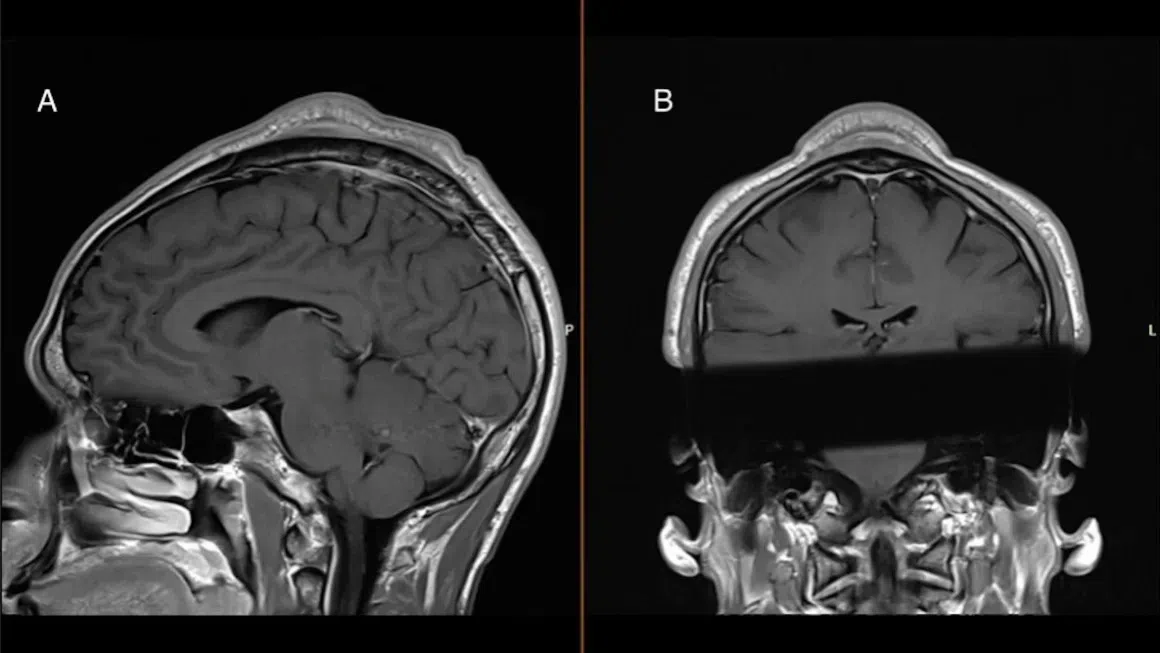

In a case report published on Oct 10 the medical journal BMJ, researchers in Denmark have identified what has been termed the “headspin hole”, which they say are an overuse injury specific to breakdancing.

In the case report, a man in his early 30s who had been breaking for almost two decades developed a benign tumour over an inch thick on his scalp from years of spinning on his head.

According to Dr Christian Baastrup Sondergaard, a neurosurgeon at Rigshospitalet in Copenhagen, the repeated friction between the scalp and the floor, combined with the pressure of headspins, leads to inflammation and scar tissue buildup. Over time, this can result in a prominent bulge.